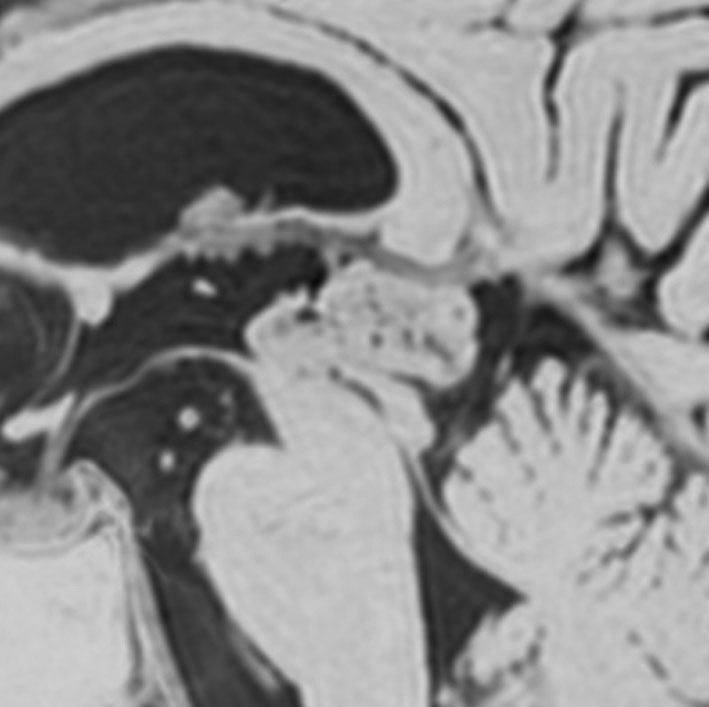

これも偶然発見された無症状の女性の小さい松果体細胞腫ですが,ほとんど実質性でのう胞がありません。右はCISSという画像です。中脳の視蓋は圧迫されて変形していますが,中脳水道がまだ閉塞していないのがよくわかります。